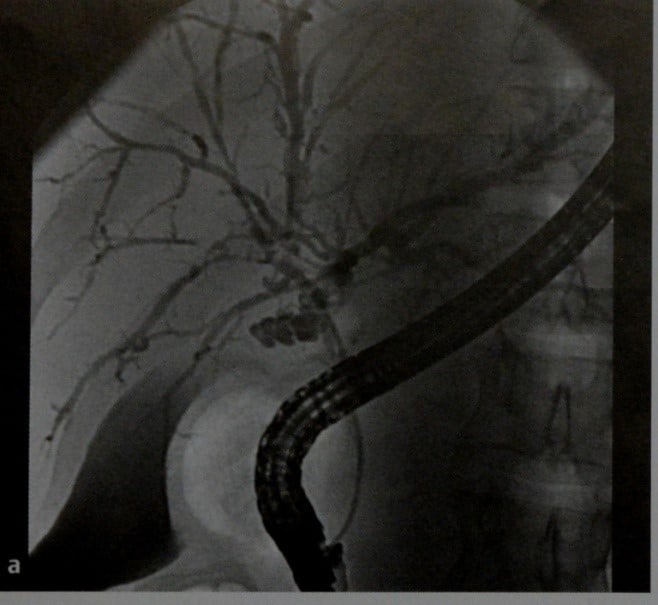

Фотографии и изображения, связанные с симптомами первичного склерозирующего холангита